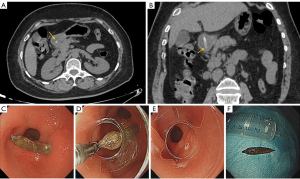

All cases in the reference reported group were inpatients. Among them, 21 (91.30%) patients showed signs of inflammation with elevated white blood cell count, procalcitonin, and C-reactive protein. In the present study group, the laboratory findings of many outpatients were not traceable. The patients in the present study group received both outpatient and inpatient treatment, including surgery (Figure 3), endoscopy (Figure 4), conservative treatment, or non-intervention with follow-up (Figure 5). For the inpatients in both groups, surgical removal is the most common treatment.

CT features of jujube pits

In total, all 25 jujube pits were detected by CT in 22 patients in the present study group when reviewing. The CT characteristic of jujube pit is high-density shaped like a shuttle with two sharp ends. The density is heterogeneous, with a higher density margin, and the density decreases inward. Low-density hollow areas of different sizes were detected in 13 Jujube pits. Mean-HU ranged from −89.92 to 153.13 HU and max-HU ranged from 156 to 315 HU (Figure 6A). Intra-reader agreement was excellent for ROI measurements of mean-HU and max-HU (ICC =0.987, P<0.001; and ICC =0.980, P<0.001, respectively). The length and width of the jujube pits ranged from 1.38 to 3.50 cm and 0.47 to 0.71 cm, respectively (Figure 6B). Intra-reader agreement was excellent for length and width (ICC =0.991, P<0.001; and ICC =0.876, P<0.001, respectively).

CT findings of perforation caused by jujube pits

The CT findings of the 11 patients with perforations are summarized in Table S4. Jujube pits piercing the intestinal wall with one sharp end or two sharp ends or jujube pits that migrated to the peritoneal space on CT directly indicated the occurrence of perforation. Indirect CT findings of intestinal perforation included thickening of the intestinal wall with abnormal enhancement, mesenteric fat stranding, localized peri-enteric gas or abscess collections, and associated intestinal obstruction. In terms of perforation sites, all 11 cases occurred in the small intestine. Except for one jujube pit perforating the duodenum, there was a subtle tendency of the perforation location to concentrate toward the terminal ileum.

The sensitivity of CT in detecting subphrenic jujube pits was 100% on retrospective reviews of CT images. However, a lower diagnostic sensitivity (66.7% in reference group and 96% in our group) is owing to radiologists’ insufficient cognition of foreign bodies (35). According to our experience, when the long axis of the jujube pit is perpendicular to the axial plane, it appears as a small ring hence jujube pits can be easily missed or mistaken for intestinal gas content for physicians or junior radiologists. Senior radiologist can be alarmed by incidental signs of fat stranding and thickening of gastrointestinal wall. With the help of multiplanar reformation, shape of jujube pit and the relationship between sharp points and the digestive tract wall are better visualized (Figures 3-5), eventually the jujube pit was detected and more information can be provided for clinical management (16). Max-HU of jujube pit ROI in this study was lower than or equal to 329 HU, which can act as a threshold value to help differentiate jujube pits from other high-attenuation materials such as metal foreign bodies.